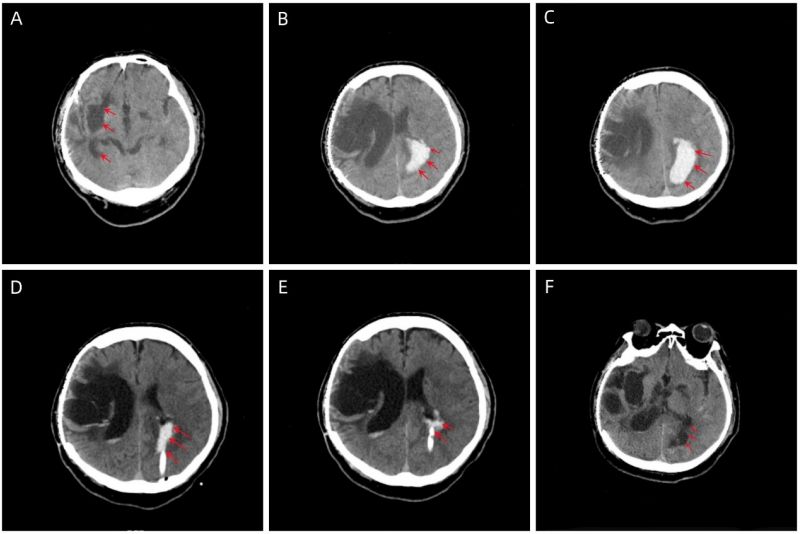

图A:既往脑出血遗留瘢痕;图B、C:术前颅脑CT可见左侧顶枕叶可见片状高密度影,侧脑室受压,局部可见低密度水肿带;图D、E:术后颅脑CT可见颅内血肿较术前减少,局部可见引流管影;图F:出院时复查颅脑CT,颅内血肿吸收完全,局部瘢痕形成。

该53岁男性患者因“意识障碍伴肢体抽搐13小时余”入院。入院后立即完善颅脑CT检查,显示其左侧顶枕叶可见片状高密度影,量约40ml,局部脑结构受压。经快速评估,患者出血量较多,需要手术治疗。经系统评估患者病情,胡佳主任医师团队决定为患者实施微创穿刺血肿引流手术。术中引流管一次顺利到位,术中抽出血性液体20ml,术后患者癫痫症状明显缓解,发作次数明显减少,发作时间也明显缩短。经过术后系统治疗,科学调整抗癫痫药物,患者很快顺利出院。